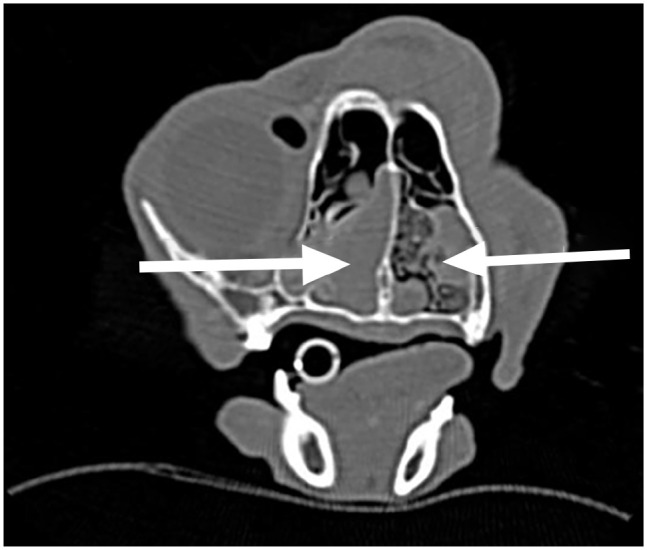

Case series summary: Described are three cats diagnosed with rhinosinusitis secondary to Mycobacterium bouchedurhonense, Aspergillus species and Alternaria species, respectively. Medical records were retrospectively reviewed to identify cats with decreased nasal airflow and mucopurulent discharge that failed to improve on antibiotic therapy of 3 months or longer duration. Surgical debridement was followed by nasal packing using 5% povidone-iodine saturated umbilical tape, which was replaced at 24 h postoperatively. At 48 h postoperatively, the rhinotomy site was closed. Systemic therapy continued in the postoperative period. All cases were minimally responsive to previous medical management. History, signalment, clinical signs, diagnostic findings, treatment, and short- and long-term outcomes were retrieved. All cats were middle-aged with outdoor access and had clinical signs that commenced during the summer months. CT revealed turbinate destruction and soft tissue densities within the nasal passages. The otic apparatuses and calvaria were intact in all cats before surgery. A repeat CT examination revealed an improvement of the proliferative tissue identified in preoperative imaging in all cases. All cats achieved successful interruption of nasal discharge and restoration of nasal airflow with follow-up times of up to 16 months postoperatively.

Relevance and novel information: To the authors' knowledge, this is the first report of the use of intranasal povidone-iodine packing in cats for the management of infectious rhinosinusitis. Surgical debridement and intranasal packing in addition to systemic therapy were successful in restoring nasal airflow and resolving nasal discharge in all cats with long-term follow-up.